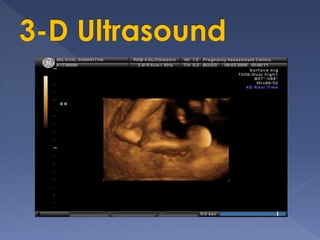

two-dimensional ultrasound (2D)

three and four-dimensional

ultrasound (3D/4D)